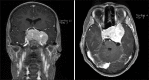

Materials and methods: We report the case of a 15-year-old girl with a huge growth hormone-secreting pituitary adenoma with supra- and perisellar extension. Furthermore, the skull base was infiltrated. In this case, we performed an endonasal transsphenoidal approach for debulking the adenoma and for chiasma decompression. We used an MRI neuronavigation (Medtronic Stealth Air System) which was registered via intraoperative CT scan (Siemens CT Somatom). Preexisting MRI studies (navigation protocol) were fused with the intraoperative CT scans to enable three-dimensional navigation based on MR and CT imaging data. Intraoperatively, we did a further CT scan for resection control.

Results: The intraoperative accuracy of the neuronavigation was excellent. There was an adjustment of <1 mm. The navigation was very helpful for orientation on the destroyed skull base in the sphenoid sinus. After opening the sellar region and tumor debulking, we did a CT scan for resection control because the extent of resection was not credible evaluable in this huge infiltrating adenoma. Thereby, we were able to demonstrate a sufficient decompression of the chiasma and complete resection of the medial part of the adenoma in the intraoperative CT images.